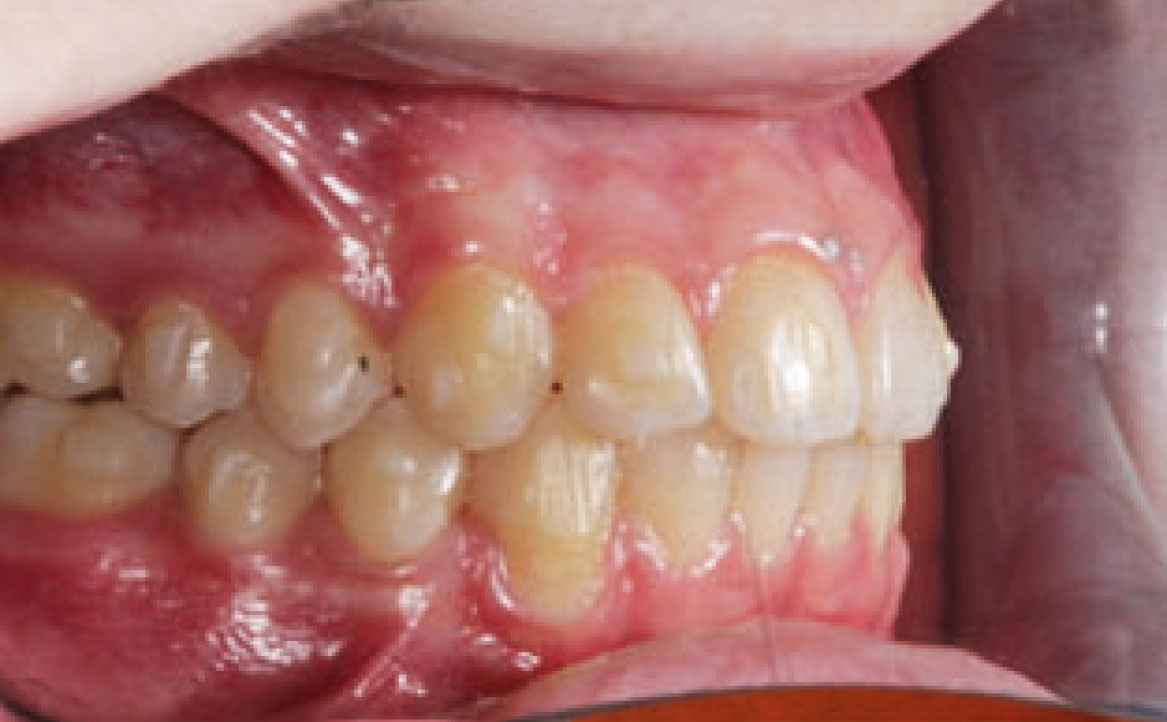

Dall’esame obiettivo intra orale si osservava una seconda classe canina destra e sinistra, una seconda classe molare destra e sinistra, e un diametro inter-canino e inter-molare ridotto sia in riferimento al mascellare superiore sia al mascellare inferiore (fig. 3A-3E).

A seguito del trattamento è stato osservato un miglioramento dell’igiene orale (fig. 5).